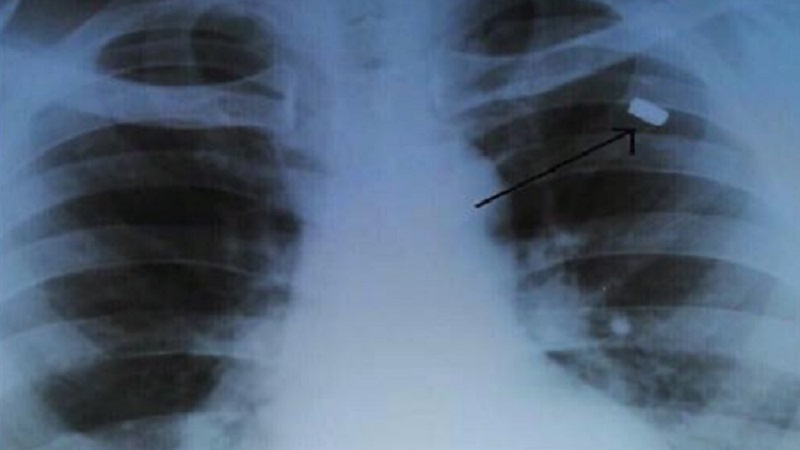

نجح أطباء من مدينة نالتشيك، عاصمة قبردين بلقار الروسية، بإجراء عملية جراحية معقدة استخرجوا فيها رصاصة